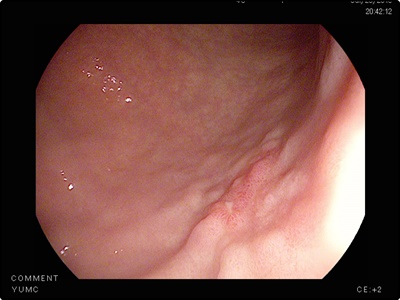

위암 초기증상: 소화기능 저하로 인한 위축성 위염

위산 분비가 감소하면서 동시에 소화기능이 저하되면 위 점막에 있는 세포가 변형을 일으키게 됩니다. 그리고 소화기능 저하라는 초기증상으로 나타나게 됩니다. 이는 위암 발생 위험도가 6배나 높습니다. 그리고 위축성 위염이 된 위는 정상인의 위로 회복이 불가능합니다.

하지만 위암으로 발전하지 않게 하도록 연속적인 관리가 필요합니다. 때문에 정기적으로 꾸준히 위내시경 검사를 하는 것이 중요합니다. 때문에 위암을 미리 예방하기 위해서는 나트륨 과다섭취를 피하는 것이 좋습니다. 가능하면 위벽을 자극하지 않도록 해야만 합니다. 위가 자극을 받게되면 위궤양을 일으키고 암세포를 생성하게 됩니다.